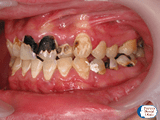

症例2

20代男性。コーラやジュースを毎日大量に飲んでいました。成分に多量に含まれている糖分はバイ菌の栄養になって口腔内で増殖します。また酸性度が高いので本来は水晶に匹敵するくらい丈夫な歯の表面のエナメル質が溶け続けます。悪い状況を続けた結果、ほとんど全ての永久歯がむし歯になってしまいました。まさしく生活習慣病の一つです。このままでは糖尿病やほかの病気も発症してしまい著しく健康を損なうことになります。

欠落していた食生活(食事内容、食事の間隔)の指導、口腔ケアを行っていくことになります。もちろんこの後むし歯の治療をしていきますがたくさんあるので大変です。予防はこうならないために必要なのです。治療にならないようにケアした方がお金や時間がなくならないのでとってもお得です。